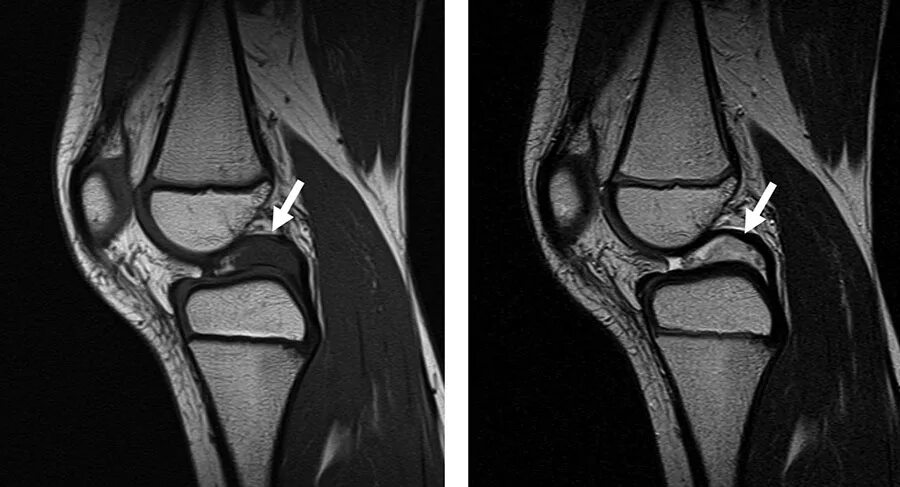

Синовиомы